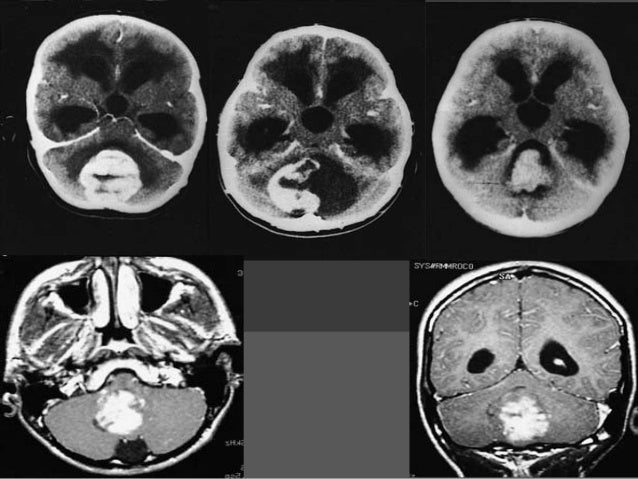

It is used to diagnose tumors, infection, inflammation, and other brain disorders. A biopsy means taking a small tissue sample from your brain and examining it under the microscope. A brain tumor is an abnormal growth of tissue in the brain or central spine that can disrupt proper a biopsy may be necessary, so a pathologist can be brought in to help identify the brain tumor type.

Specimens are taken from normal tissue, edema, solid tumor and central necrosis.

A stereotactic biopsy is a surgical procedure where a thin needle is inserted into the brain by a neurosurgeon to extract a small piece of tissue to examine. A biopsy is a major procedure, and it is the most definitive test for brain tumor diagnosis. A brain biopsy can help doctors diagnose brain illnesses, allowing them to devise treatment plans. These are generally seen in stereotactic biopsy: